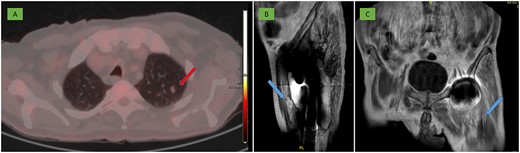

After surgery, a nodule compatible with pulmonary metastasis was identified on PET-CT (Fig. 6A) and on MRI other similar metastases were also observed adjacent to the gluteus maximus and in the anterior rectus muscle (Fig. 6B and C).

(A) PET-CT: 10 mm nodule in the left pulmonary apex with incipient metabolic activity suggestive of malignancy (arrow). (B, C) MRI: deep residual lesional focus in the anterolateral region dependent on the anterior rectus muscle (arrow).